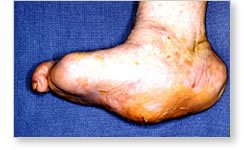

progresses to its chronic stage. During this stage the following symptoms may be

present: a foot which is deformed, and noticeably different then the other foot;

a collapsed arch; bones which abnormally protrude against the skin, possibly

causing the skin to breakdown and ulcerate; swelling and inflammation of the

foot; and there may be no pain present, or in some patients the pain is intense,

due to the amount of bone and joint destruction present.